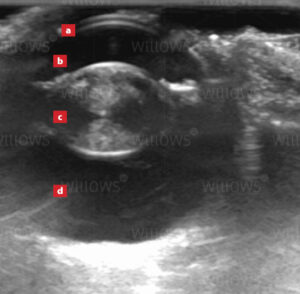

Ultrasound scanning provides superb detail in soft tissues allowing examination of parts of the body that are not easily seen on X-rays, i.e. internal structure of the heart and the eye, the contents of the abdomen and the muscles in the limbs. Conventional X-rays cannot distinguish between the outside wall and the inside cavity of hollow, fluid-filled organs, i.e. the bladder, whereas ultrasound allows these two separate parts to be identified and examined in detail.

The majority of ultrasound scans performed at Willows are of the abdomen. Ultrasound provides superb detail about the internal structure of the organs, and differentiates between fluid and solid tissue. It is invaluable when there is abnormal fluid (called ‘ascites’) within the abdomen. In addition, ultrasound allows assessment of movement in real time, and so stomach and gut movement can be seen. Sampling of the different tissues and fluids within the abdomen can be performed with increased safety under ultrasound guidance, rather than being carried out ‘blind’. Below is a video of an ultrasound scan of urine entering the bladder. The urine enters the bladder via the tubes from the kidneys (the ureters) and it can be seen squirting into the bladder as the red coloured jet (on this Doppler colour-flow scan the red colour indicates a rapid flow of fluid.